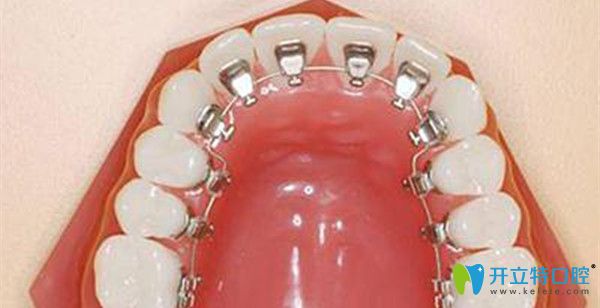

舌側(cè)保持器的優(yōu)缺點(diǎn)

優(yōu)點(diǎn):相比鋼絲保持器和透明保持器而言,舌側(cè)保持器會(huì)更加方便,它固定在牙齒內(nèi)側(cè),外觀上看不出阿里,也不需要經(jīng)常摘下來(lái),位置固定療效也會(huì)更好。